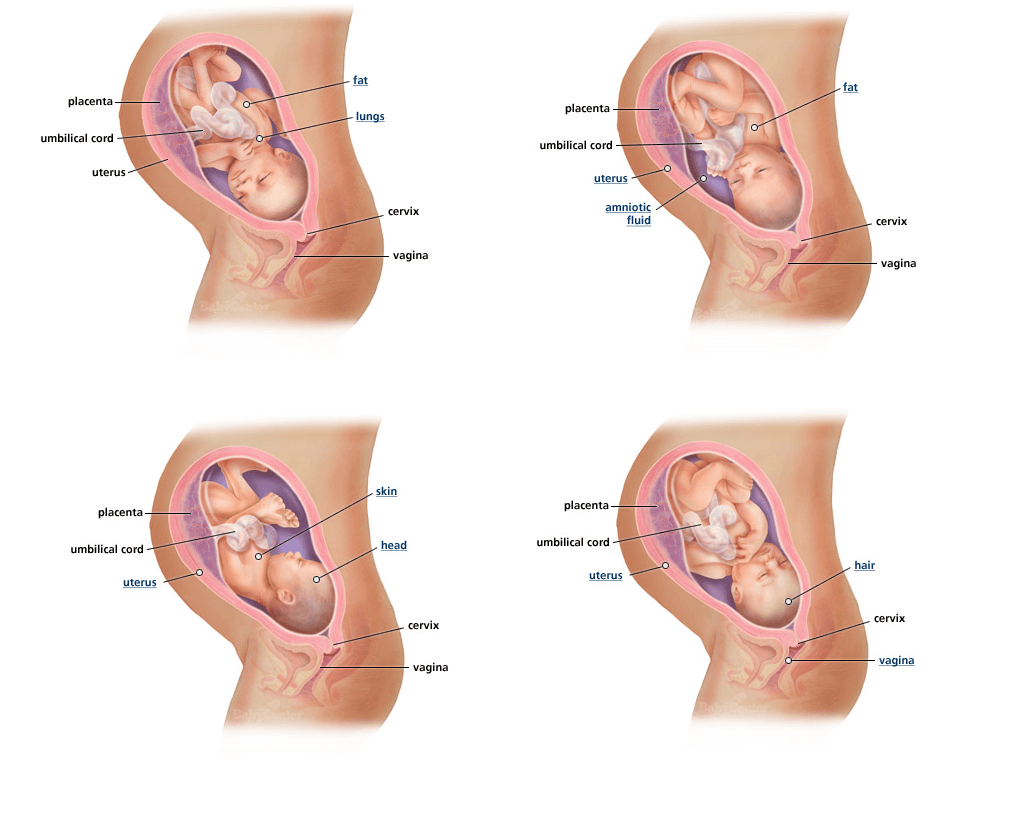

5 aylık hamileyim bebeğimin hareketlerini hissetmiyorum. Hamileliğin ikinci 3 aylık sürecinde yani 2 trimester de ise tekmeler daha. Merhaba bende 20 3 gunluk hamileyim bebegim ilk bebek olmasina ragmen hareketlerini cok erken haftalarda hissetmeye baslamistim hergun onun hareketleriyle oynardim ancak dun ve bugun bebegim hic hareket etmiyor yada ediyorda benmi hissetmiyorum cikolata yiyince 1 2 saat icinde hemen tepinmeye baslardi dun yine yedim ama yine hareket hissetmedim suan uyandim yine tepki yok korkuyorum bebegimi. Slm ben 21 haftalık hamileyimbu ilk gebeliğim hergün hissediyorum bebeğimin hareketlerini o kadar güzel bi duygu ki. Bebeğimin hareketlerini hissetmiyorum yada bebek hareket etmiyor diyenler için.

Merabalar ben 24 haftalık hamileyim bebeğimin tekmelere hissedemiyorum günde ya bir yada iki defa hissediyorum normal mi tessekkürler gecen hafta randevum. Halime halime h h soruyor. En çok ne yediğinizde içtiğinizde bebişleriniz hareket etmeye başlar. Hamile olanlar yardım edin 6 aylık hamileyim ama çocuğun hareketlerini hissetmiyorum çevremdeki insanlar tekmelerini felan hissettiklerini söylüyor ama bende o kadar fazla olmuyor doktora gittim bebekte herhangi bir sorun gözükmüyor dedi.

Ben hamileyim bebeyimi hisediyorum ama iki defa doktora gitim. Haftasına gelindiğinde bebeğin hareketleri daha da belirginleşmeye başlar ancak yine de bazı anne adayları bebeğin hareketlerini bu haftalarda hissedemezler. Kızım 6 buçuk aylık emekleyemiyor. Ben 14 haftalık hamileyim ve bu benim ilk gebeligim ve şuan hiç birşey hissetmiyorum genelde ilk gebeligi olanlar 5 ayda bebegi hissedebiliyorlarmış.

Hafta itibarı ile hissetmeye başlayabilirler. 17 haftalık hamileyim bebeğimin hareketlerini hissetmiyorum. Bebeğin hareketlerini kaç haftalıkken hissederiz. 17 haftalık hamileyim bebeğimin hareketlerini hissetmiyorum.

28 4 haftalık hamileyim bebeğim fazla hareket etmedi normal mi. İlk defa anne olacak olan kadınlar bebeklerinin hareketlerini 24. Sebebi ise bağırsak hareketlerinin bebeğin hareketleri ile karışabileceğinden. Kizlar bi kizim olucak 20 5 haftalik hamileyim ve hareketlerini fazla hissesemiyorum gun icinde hissediyoeum bi iki kez ama baska yok normalmi yarin saglik ocagina gidicem ama icim rahat degil.